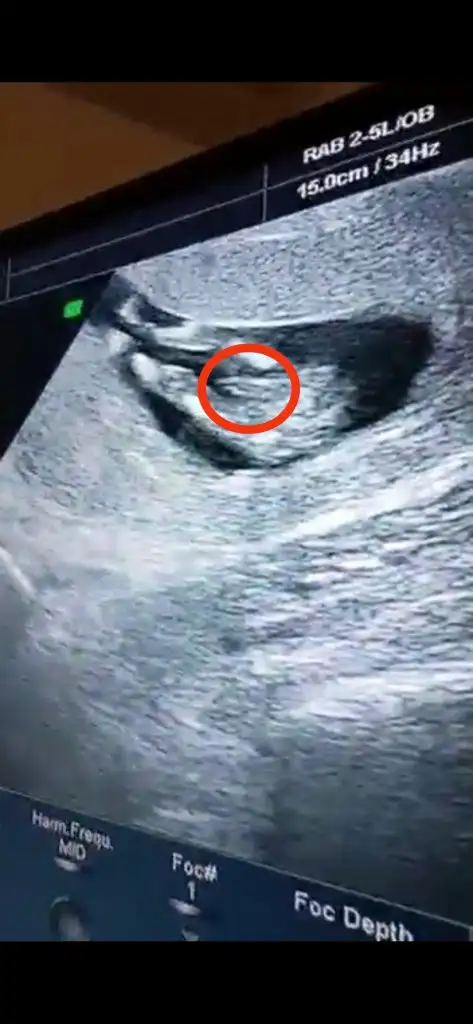

Ay bu resmen pipiKizlar Selammm, umarım herkes ve bebisleri iyidir. Dün doktor kontrolümüz vardi. 2'li tarama testimiz temiz herşey yolunda görünüyor şuan. Bir dee cinsiyetini öğrendik, Oğlum oluyormuş.

Ne güzel maşallah öğrenmişsiniz bende sabırsızlıkla ikili tarama testini bekliyorum .oğlunuzu sağlıcakla kucağınıza alın inşallah. Kaçıncı haftanızda yaptırdınız ikili tarama testini . En son 9+2 de muayene olmuştum 3 hafta sonra çağırdı doktorum ikili tarama testi için.Kizlar Selammm, umarım herkes ve bebisleri iyidir. Dün doktor kontrolümüz vardi. 2'li tarama testimiz temiz herşey yolunda görünüyor şuan. Bir dee cinsiyetini öğrendik, Oğlum oluyormuş.